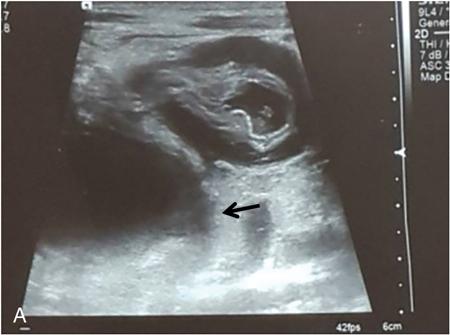

Rashmi Dixit, Anju Garg Abdominal masses are a common clinical problem in children, arising from virtually any abdominal organ. Masses arising from the gastrointestinal (GI) tract are not uncommon. They may be congenital or developmental, inflammatory, infective, idiopathic or neoplastic in nature. A high index of suspicion is necessary so as to ensure an early diagnosis and appropriate management. Imaging, therefore, plays a vital role in identifying the location, nature and extent of the mass lesion. Ultrasound (US) is the first-line imaging method for GI masses, like for most paediatric abdominal masses. It does not require sedation and is nonionizing which are important considerations in the paediatric population. US findings may be diagnostic in certain masses when no further imaging is required. Computed tomography (CT) plays an important role in complete evaluation of GI masses especially where US is either not diagnostic or the full extent and nature of the mass needs to be delineated, especially prior to surgery. It requires the administration of intravenous contrast and preferably oral contrast as well. Sedation may be required and it carries the risk of radiation exposure. Each study, hence, needs to be tailored to answer the clinical question at hand, while ensuring the lowest possible radiation exposure. Magnetic resonance imaging (MRI) provides excellent contrast resolution, which along with its nonionizing nature makes it a very attractive imaging technique. However, due to the relatively long imaging time requiring sedation, sensitivity to motion both respiratory and bowel and limited availability it is generally used as a problem-solving tool. Plain films and contrast studies currently have a very limited role in the evaluation of GI masses. Plain films may be diagnostic in masses like teratomas, while contrast studies may be required for mucosal abnormalities and small endoluminal masses like polyps. Enteric duplication cysts can occur along any portion of the GI tract from the pharynx to the rectum. They are found most often in the ileum (33%). The other sites are the oesophagus (20%), colon (13%), jejunum (10%), stomach (7%) and duodenum (5%). The incidence is reported to be around 0.2% of all children, with a slight male predominance. Duplication cysts are thought to arise between the 4th and 8th weeks of development; however, their aetiology is unknown and several different theories have been proposed. In 16%–26% cases there may be associated spinal defects, cardiac or urinary malformations. Other associated GI anomalies may be seen in about 10% of cases. Duplication cysts typically lie along the mesenteric border of the gut. They have smooth muscle wall which they share with the adjacent gut, as also the blood supply. On histopathology, three classical features are seen: an epithelial lining with GI mucosa, a smooth muscle covering and a close attachment to the GI tract due to a shared common wall. Although the mucosal lining does not necessarily match with the adjacent portion of the gut, nonetheless, duplications are named after the portion of the gut to which these are closely related. About 20%–30% of these duplication cysts contain ectopic gastric mucosa which is more common in oesophageal and small intestinal duplication cysts. Ectopic pancreatic mucosa may also be seen, most often in gastric duplication cysts. Morphologically they may be cystic or tubular with the former accounting for 80% and the latter for 20%. While cystic duplications mostly do not communicate with the adjacent gut, tubular duplications that run parallel to the GIT often do, hence in these cases connection with GIT must be demonstrated for operative planning. Duplication cysts may be multiple in 1%–7% of cases usually occurring in the same segment of the GIT. An atypical duplication cyst is an isolated duplication cyst which is completely separated from the GIT and has no communication or shared wall with the gut. They are extremely rare and thought to be the result of a vascular injury. Although duplication cysts may remain asymptomatic till adulthood they mostly present within the first year (70%). Almost 85% present by the second year. Clinical features depend not only on the size and location, but also on the presence of any ectopic mucosa and complications. Pharyngeal and oesophageal cysts may present with respiratory distress or dysphagia. Infection and rapid growth may cause retrosternal pain or haemoptysis. Gastric and intestinal duplications cause nonspecific symptoms like recurrent abdominal pain nausea, vomiting, distention or a palpable lump. High pressure inside the cyst consequent to accumulation of secretions is thought to be responsible for the recurrent abdominal pain. Obstruction due to intussusception or extrinsic compression may occur. Presence of gastric mucosa is associated with complications like inflammation, bleeding, ulceration and perforation. US is most useful for the diagnosis of abdominal duplication cysts and sometimes may demonstrate these on an antenatal scan. MR and CT are mainly used for oesophageal duplication and for planning surgery. Endoscopic trans oesophageal ultrasound may be informative for oesophageal duplications but is not a part of routine practice. Classical US features in uncomplicated duplication cysts include: a unilocular cystic structure in close proximity to the bowel. The cyst has a relatively thick wall which has a hyperechoic inner lining representing the mucosa and an outer hypoechoic rim produced by the smooth muscle layer (muscularis propria) – the so-called ‘gut signature’ sign. This sign is also referred to as the ‘double-wall’ or ‘muscular rim’ sign. (Fig. 7.7.1) Though, most characteristically described for duplication cysts, it may sometimes be seen in some other cystic lesions such as a complicated mesenteric cyst, Meckel’s diverticulum or torsed ovarian cyst. Some US signs described recently are: the ‘five layered cyst wall sign’ and ‘Y configuration of the muscle wall sign’. It has been shown that with the use of high frequency US transducers (12–18 MHz) the wall of the duplication cyst can demonstrate the same five layered wall structure as the normal GIT. From inside to outside these are: the innermost mucosa which is hyperechoic, muscularis mucosa (hypoechoic), hyperechoic submucosa, hypoechoic muscularis propria and the outermost serosa which is hyperechoic. If all these five layers can be identified in a cyst it is diagnostic of an enteric duplication cyst; however, the sign is difficult to demonstrate (Fig. 7.7.2A and B). The second sign arises because a duplication cyst shares its wall with the adjacent gut. Splitting of the common muscularis propria between the cyst and the adjoining bowel loop results in the Y configuration of the muscle layer on US, reflecting one of its important histological features. When this is seen, it is possible to confidently diagnose an enteric duplication cyst as this sign has not been demonstrated in other cysts. The ‘Y configuration sign’ can be particularly valuable in complicated cysts In addition, since US is a real time examination it also allows visualization of peristalsis of the cyst wall which is seen as a transient change in the cyst shape and contour due to contraction of the cyst wall (Fig. 7.7.3A and B). This requires the transducer to be kept stationary over the cyst for some time Most duplication cysts are anechoic but some echoes due to mucinous fluid or septations can be seen at times, and do not imply complications. Complications include haemorrhage (due to ectopic gastric mucosa), enzymatic destruction of the mucosal lining, inflammation (due to ectopic pancreatic tissue) and infection. In these cases, fluid levels or echogenic debris can be seen within the cyst with a thick hypervascular wall which may lack layers (see Fig. 7.7.2B). In these cases, the Y configuration sign can help to suggest the correct diagnosis. The inflammatory changes may extend to the surrounding mesenteric fat as well, which becomes hyperechoic. Duplication cysts near the ileocecal valve, can act as a lead point for intussusception. Atypical or isolated duplication cysts, may just produce the pseudokidney sign. The important US features of duplication cysts are listed in Box 7.7.1. Key Ultrasound Signs of Duplication Cysts CT is not performed for the diagnosis of duplication cysts, however, it can demonstrate the location, anatomical relationships, exact extent and the associated anomalies. On CT evaluation a cystic mass closely related to the adjoining GI wall is seen. The wall shows mild enhancement. A complicated duplication cyst showing internal high attenuation, air foci, thick enhancing wall and surrounding inflammation suggests infection (Fig. 7.7.4A and B). Internal high attenuation alone, however, could be due to proteinaceous contents or haemorrhage and does not imply infection on its own. MR is also not generally used as a diagnostic tool due to long examination times requiring sedation but is especially useful to demonstrate the cystic nature of thoracic duplications. Duplications cysts show hypointense signal on T1W sequences and very high signal on T2W images. Both CT and MR may be used prior to surgery. MR may have an additional value in assessment of foetal abdominal cysts. Differential diagnosis includes other cystic lesions such as mesenteric, omental, ovarian and choledochal cysts. In patients with an antenatal diagnosis, although the optimal time for resection is not defined, it is suggested that early resection within the first 6 months be considered. Treatment of asymptomatic duplication cysts remains controversial, however, since early elective surgery is associated with less morbidity and a shorter hospital stay than excision in symptomatic cases, it should be preferred. In addition, complications such as obstruction or massive bleeding may be life threatening and there is a potential risk for malignant transformation in adults. The cyst can be removed alone, but if there is a communication with the adjoining gut its resection will be required. Currently, minimally invasive surgery is becoming the procedure of choice. Complete excision is important to avoid cyst recurrence or subsequent malignant changes. Hypertrophic pyloric stenosis was earlier believed to be a developmental anomaly but is currently thought to be acquired disorder. It is characterized by hypertrophy of the circular muscle layer of the pylorus. This results in thickening and lengthening of the pylorus ultimately progressing to gastric outlet obstruction. The etiopathogenesis of this disorder is unknown but postulated mechanisms include abnormal innervation of the pylorus and duodenal irritation due to hypersecretion. Various genetic and environmental factors such as maternal smoking and use of erythromycin have also been implicated. Several ultrastructural anomalies have been identified in the muscle layer including abnormal nerve endings, decreased synthesis of nitric oxide, reduction in the number of cells of Cajal and an increased production of insulin-like growth factors. These factors are thought to cause muscle hypertrophy and failure of muscle relaxation. The incidence of HPS is about 3 per 1000 live births with male to female ratio of 4–5:1. Patients usually present between 2 and 6 weeks of age. The child is typically normal at birth and, subsequently develops non-bilious vomiting around 2–3 weeks of age. There may be a small lump palpable in the epigastrium, the so called ‘pyloric olive’, in nearly 80% of cases. Also, peristalsis may be seen traversing the epigastrium. If vomiting persists, dehydration and hypochloraemic alkalosis can develop. In the presence of a classical history and examination findings, the diagnosis is often made clinically and imaging is only used to confirm the diagnosis. US allows visualization of the pyloric canal morphology as well as behaviour during dynamic evaluation. Ultrasonography is performed with a high-frequency transducer ranging between 6 and 15 MHz. The child is placed supine and the examination is best performed with a moderately fluid-filled stomach. The first step is to localize the gallbladder as the pylorus lies posteromedial to the gallbladder. Another useful trick is to first localize the upper pole of the right kidney and then move the transducer medially towards the xiphoid to identify the pylorus. The transducer is then angulated so that the pyloric canal is well visualized in long axis. Correct positioning so that the pyloric canal is seen as a straight line is important to ensure that measurements are not performed in a tangential plane which can result in fallacious increase in muscle thickness. Sometimes a gas distended stomach may preclude visualization of the pylorus. In this case, shifting the child to an oblique position so that the right side is placed inferiorly allows fluid to move into the antrum which acts as an acoustic window. A markedly distended stomach can displace the pylorus posteriorly making it difficult to visualize. In this situation moving the child so that the left side is down or prone positioning may help localize the pylorus. Distention of the stomach with water rather than milk may be a better option as milk may at times also cause artefacts. A nasogastric tube may be used to fill up the stomach when necessary. The most important diagnostic feature of HPS is thickening of the muscle layer of the pylorus seen as hypoechoic curved bundles between the antrum and duodenal cap. A number of signs that have been described on sonography in HPS include the ‘empty cervix’ sign as the hypertrophied muscle mass indents the fluid filled antrum and duodenal bulb mimicking the appearance of cervix in longitudinal section (Fig. 7.7.5). The hypertrophied pylorus gives appearance of a ‘doughnut or a target’ in transverse section. The ‘antral nipple’ or ‘mucosal nipple sign’ refers to redundant pyloric canal mucosa protruding into the antrum. This can be seen as an echogenic structure protruding into the fluid filled antrum (Fig. 7.7.6). The fluid trapped between the mucosal folds in the centre of an elongated pylorus may be seen as two sonolucent lines in the centre referred to as the ‘double track sign’. Measurement of muscle layer thickness provides objective assessment of pyloric thickening. A muscle layer thickness of more than 3 mm is considered abnormal. This should be measured from the outer echogenic edge of the mucosa to the outer edge of the muscle on both transverse and longitudinal scans. A muscle wall thickness of less than 2 mm is considered normal while a thickness between 2 and 3 mm is considered equivocal as it can be seen in other conditions like pylorospasm or gastritis besides HPS. Pyloric canal length of less than 14 mm is thought to be unequivocally normal. A pyloric canal length of more than 15–17 mm is also considered diagnostic for HPS (Fig. 7.7.6). However, the measurement of canal length is much more difficult to perform and subject to variability, hence this should not be used alone to make the diagnosis of HPS. Total diameter of the pylorus over 13 mm and pyloric volume measurements have also been suggested, but muscle thickness measurement remains the most accurate In addition, real-time observation of the pyloric behaviour is also important. The stomach tends to be markedly distended and shows increased peristalsis with failure of gastric contents to pass into the duodenum. The other hand a wide-open pylorus with normal passage of contents into the duodenum excludes the diagnosis of HPS (Box 7.7.2). Key Ultrasound Features of Hypertrophic Pyloric Stenosis There is a higher incidence of renal anomalies in these patients and hence kidneys should be examined once diagnosis is established. Pitfalls in sonographic diagnosis include non-visualization of the pylorus due to an overdistended stomach pushing it posteriorly, tangential views of the pylorus or pylorus spasm producing a pseudo thickening of the pylorus. Hence it is important to make sure that the pylorus is correctly imaged and the entire pyloric length is visualized in longitudinal plane. As opposed to pylorus spasm the thickening and the appearance of pylorus in HPS tends to persist, while pylorospasm is transient and generally resolves within 30 minutes. If the muscle layer measures 2–3 mm in thickness and the pylorus does not relax during the US examination clinical follow up and repeat US examination may be advisable. Borderline measurements are more likely to occur in preterm infants. Some authors have provided measurements of the pyloric length and muscle thickness correlated with the age and weight of the child which may be helpful in small and premature patients. In equivocal cases, it is preferable to perform a repeat examination rather than erroneously make a false-positive diagnosis, as HPS is not a surgical emergency. A barium study may be performed if the US examination is inconclusive. Use of a nasogastric tube is preferred as it allows a controlled filling of the stomach with barium. The upper GI barium study shows delayed emptying of the stomach. The pyloric canal is elongated and narrowed visualized as a curved streak of barium directed upwards and posteriorly, referred to as the ‘string sign’. This combination of narrowed pyloric canal along with elongation is the most important feature of HPS on contrast studies. A ‘double string sign’ is produced when barium is caught between the folds of mucosa overlying the hypertrophied muscle. ‘Antral beaking’ refers to a mass impression upon the antrum with a streak of barium entering the narrowed pyloric canal. The hypertrophied muscle may indent the gastric antrum as well as the duodenal bulb producing the ‘shoulder sign’. Disruption of the antral peristalsis may result in a small outpouching along the lesser curvature of stomach producing the ‘pyloric teat’ sign. The stomach shows hyperperistalsis on fluoroscopic examination which is sometimes referred to as the ‘caterpillar sign’ (Box 7.7.3). These signs may sometimes be seen in pylorospasm but are not persistent. Therefore, it is important that the study is of sufficient duration to establish the persistence of findings. Any the residual barium must be aspirated if a nasogastric tube has been placed, in order to avoid aspiration. Key Upper GI Features of Hypertrophic Pyloric Stenosis The treatment of HPS is surgical, that is, Ramstedt’s pyloromyotomy. Postoperatively, in the first week, the muscles may remain same in thickness or even thicker than that prior to surgery. The muscle thickness gradually returns to normal with the anterior part of the muscle normalising first followed by the posterior portion. The anterior portion usually returns to a thickness of 3 mm within 3 months whereas the posterior portion may take up to 5 months to normalize. This is related to the usual anterior surgical approach. The gastric emptying, however, returns to normal within 2–3 days. An upper GI examination may also be used to assess gastric emptying postoperatively and to exclude gastro-oesophageal reflux if vomiting persists. GI polyps are commonly seen in childhood between 2 and 5 years of age and are the most common cause of painless rectal bleeding in children. Juvenile polyps are the most common type of polyps that are seen in children accounting for about 80% of the polyps. The term juvenile refers to the histology of the polyp rather than the age at which they occur. Histologically these lesions represent benign hamartomas. Diagnosis is made via rectal examination or sigmoidoscopy. Radiological examination is rarely required for diagnosis. Polyps in the distal colon and rectum can be easily resected via endoscopic polypectomy. Inflammatory polyps are commonly seen in children with inflammatory bowel disease. Most of these polyps are actually pseudo polyps formed by hyperplastic and inflamed mucosa in areas of inflammation and mucosal injury. They may reach large sizes but are not pre-malignant. Imaging reveals evidence of inflammatory bowel disease along with polyps. Juvenile polyposis syndrome is an inherited condition characterized by multiple juvenile polyps. The following criteria must be met for diagnosis of JPS (a) more than 5 juvenile polyps in the colon or rectum (b) juvenile polyps in other portions of the GI tract (c) any number of juvenile polyps with a positive family history. Single juvenile polyps are not a feature of juvenile polyposis syndrome. JPS has been categorized into 3 types depending on the clinical features and age of onset. Diffuse juvenile polyposis of infancy presenting in children up to 3 months of age. generalized juvenile polyposis with polyps throughout the GIT and juvenile polyposis coli (JPC) with polyps only in the colon beginning in children and adolescents. Children can present with diarrhoea, rectal bleeding, intussusceptions or anaemia. The diagnosis is usually established by colonoscopy. Double-contrast barium enema or CT colonogram can also demonstrate multiple polyps within the colon. Peutz-Jeghers syndrome is rare autosomal dominant disorder characterized by hamartomatous polyps throughout the GI tract. Mutation of ATK tumour suppressor gene is seen in some cases. Histologically these polyps are characterized by a smooth muscle core arising from the muscularis mucosa. Although polyps occur anywhere in the GI tract, they are commonest in the small bowel. They can be sessile or pedunculated and being firm in nature (due to the smooth muscle core) are particularly prone to intussusception. They may also present as GI bleed and anaemia Although the polyps of PJS are benign hamartomas the syndrome is associated with an increased risk of malignancy (adenocarcinoma). The diagnosis of PJS can be made if there are 2 or more histologically confirmed PJS polyps, any number of PJS polyps along with the typical mucocutaneous pigmentation, a family history of PJS with any number of PJS polyps or the presence of mucocutaneous pigmentation with family history of PJS. Because of the presence of small bowel polyps CT enterography, MR enterography and small bowel enema also have an important role to play in the diagnosis. The polyps are seen as sessile or pedunculated intraluminal filling defects on these studies. They may also be seen as the lead point of an intussusception (Fig. 7.7.7). Endoscopy and colonoscopy are used to establish the diagnosis. Video capsule endoscopy is especially useful to identify the polyp burden in the small bowel. The treatment is aimed at removing the larger polyps either surgically or endoscopically so as to avoid obstruction.